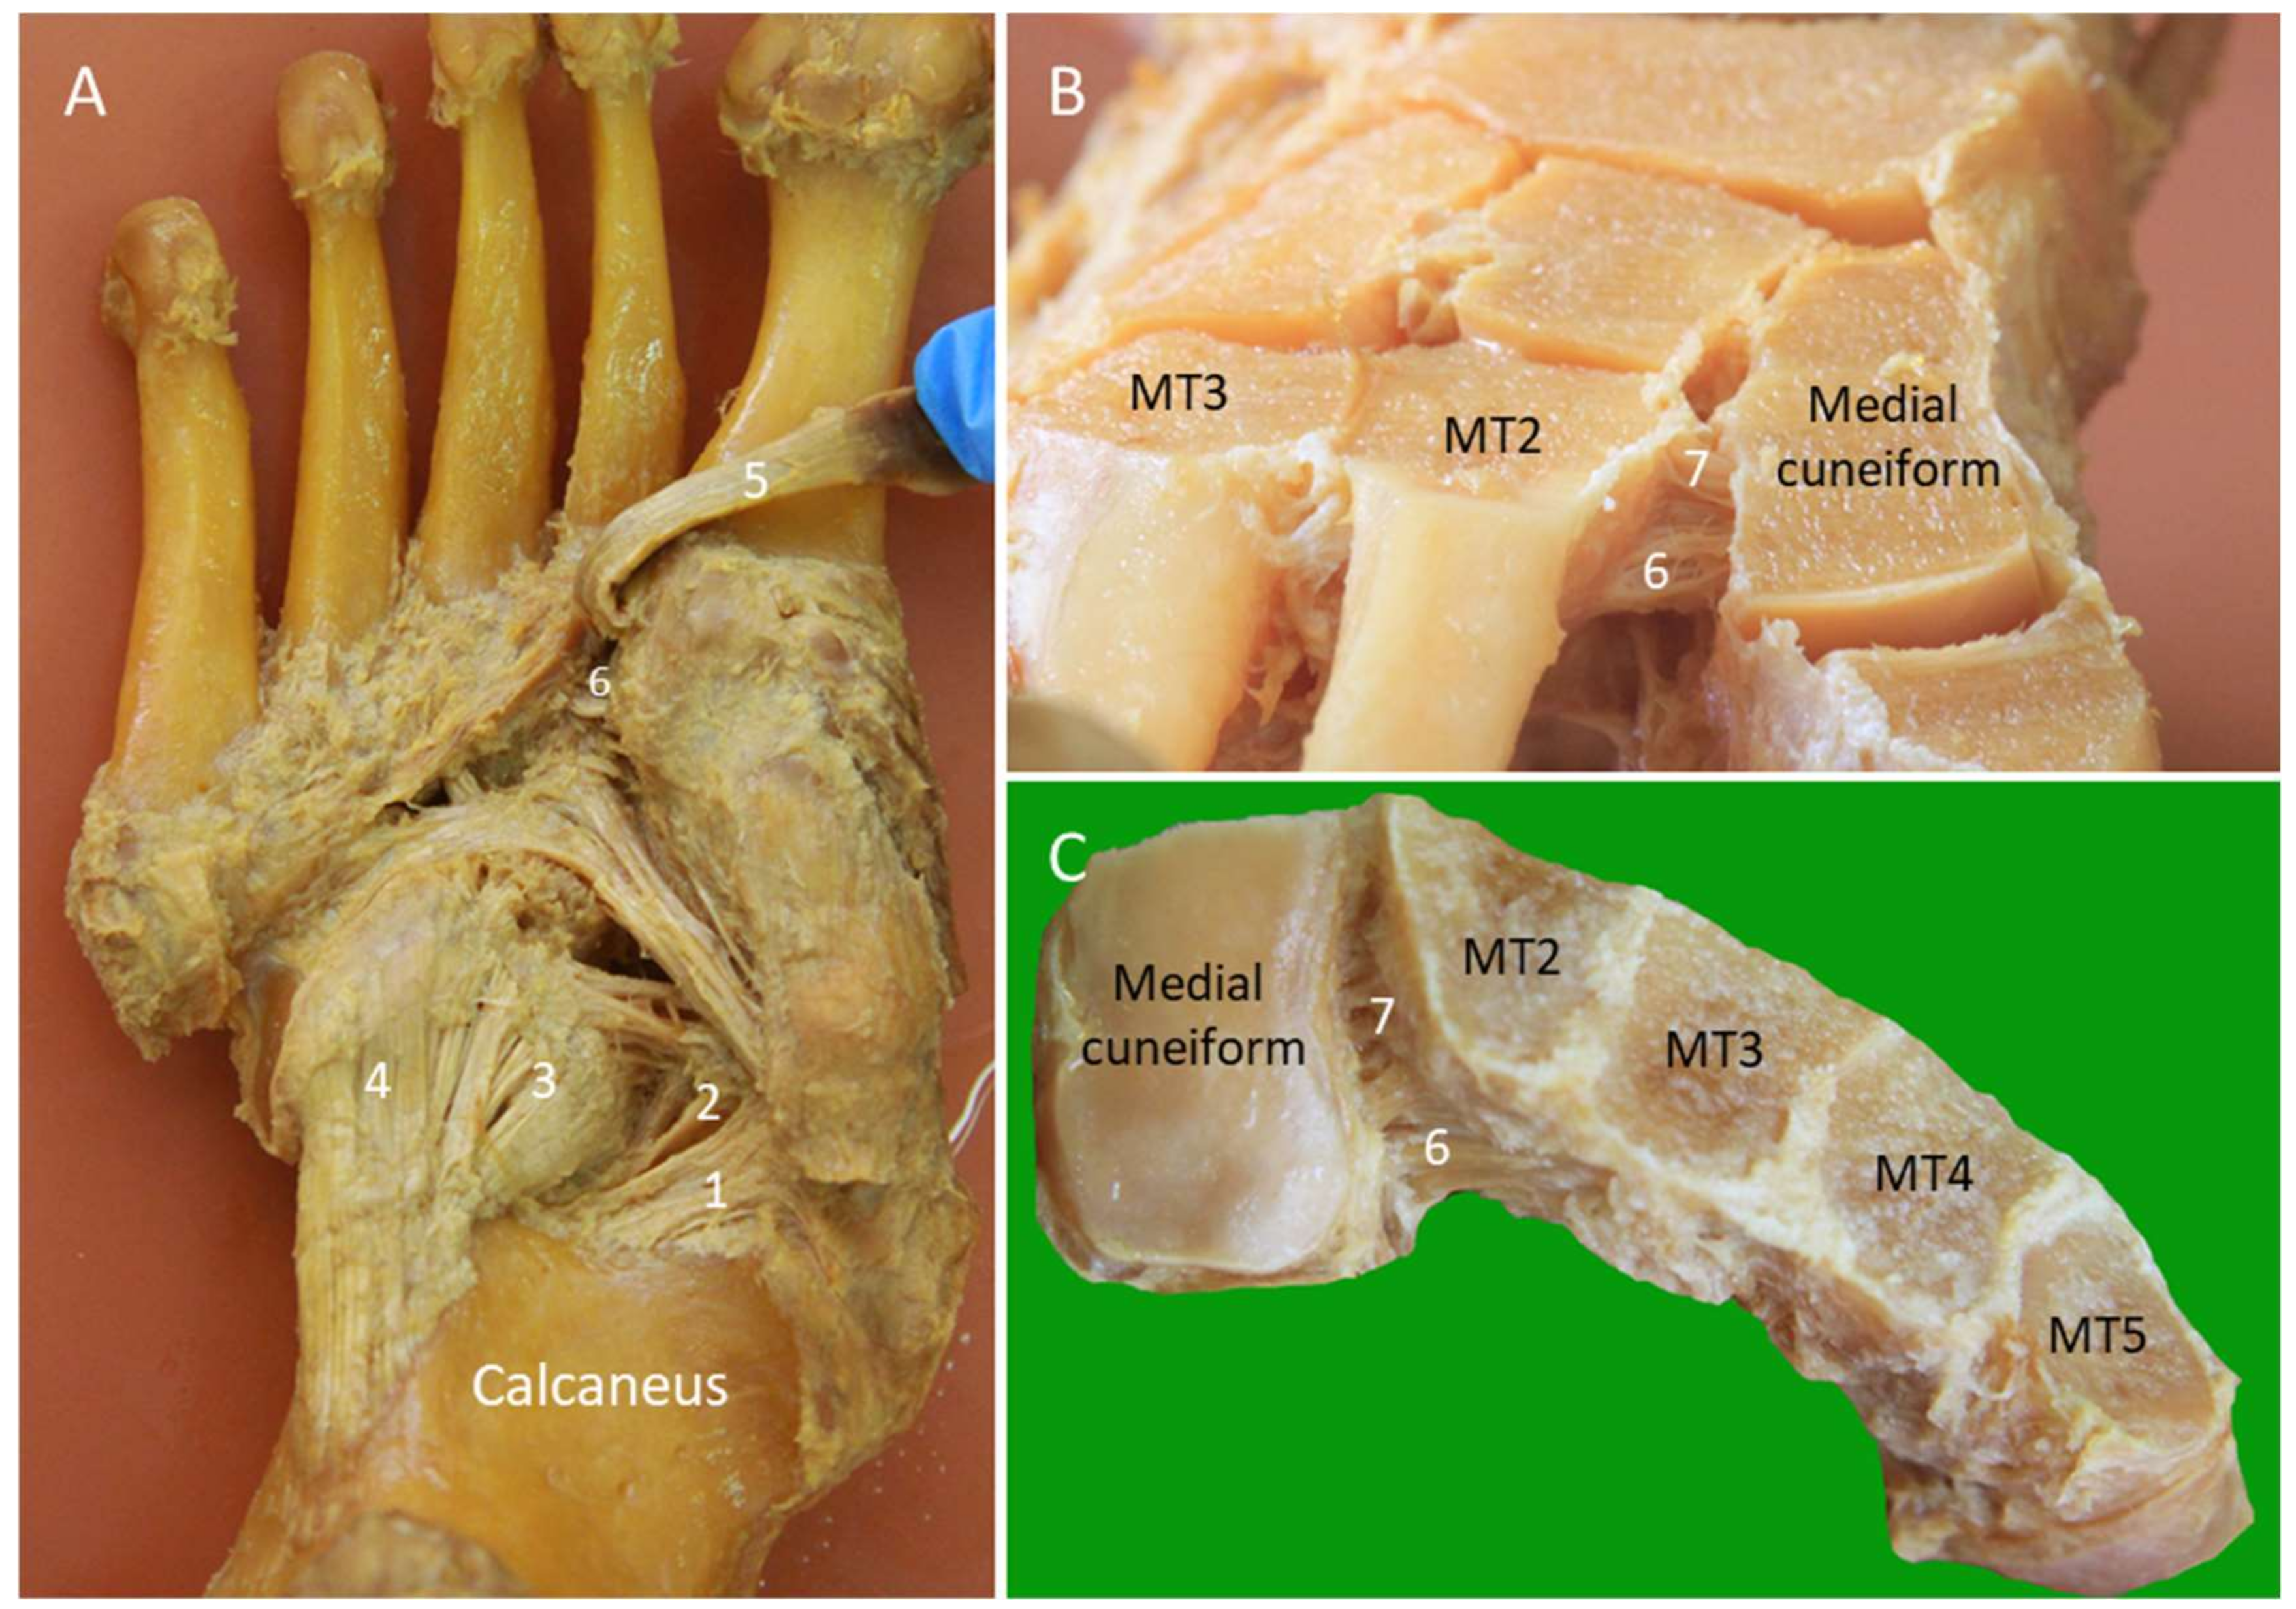

2.10. Lisfranc Ligament Complex

2.10.1. Anatomy

2.10.2. Scanning Technique

2.10.3. Clinical Relevance